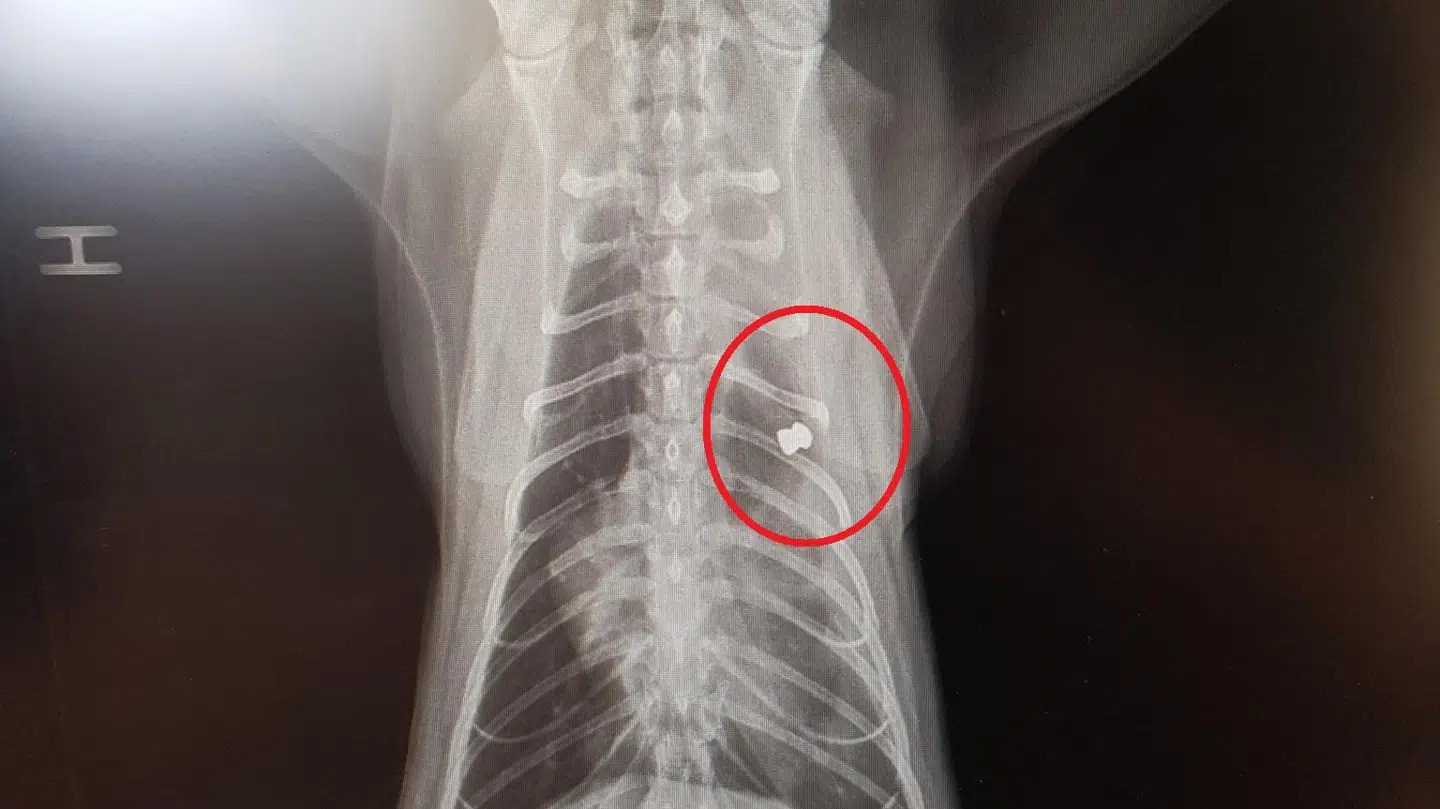

Amigos krop var fyldt med hagl. 24 hagl for at være helt præcis. Rikke Fjordbak Ravn forklarer, at familien – ligesom dyrlægen – var meget forundret over billederne. De havde aldrig set noget på katten, der indikerede, at den var fyldt med hagl.

»Han havde aldrig set noget lignende. Nogen har skudt den på klos hold med et haglgevær,« fortæller hun.

De 24 hagl har formentlig siddet i katten i flere år.